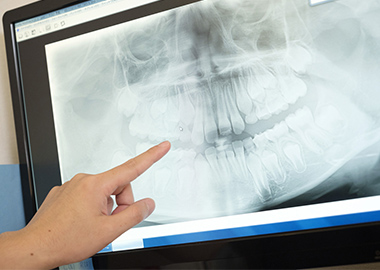

歯科用CTスキャンやセファロレントゲン、口腔内スキャナー(iTero,シャイニング)など、AIによる最新のデジタル技術を駆使して、高精度な分析データを基に、精密な診断を行っています。

患者様の歯並びやライフスタイル、要望に合わせた適切な治療計画をご提案をいたします。